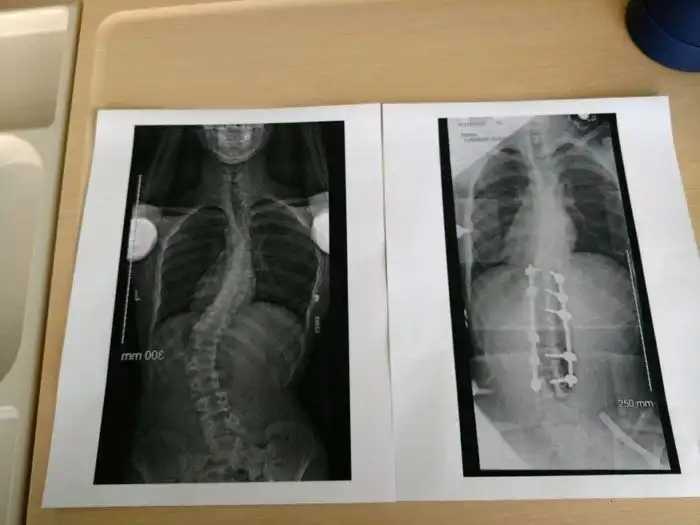

11. «Спина моего брата до и после операции по исправлению сколиоза»